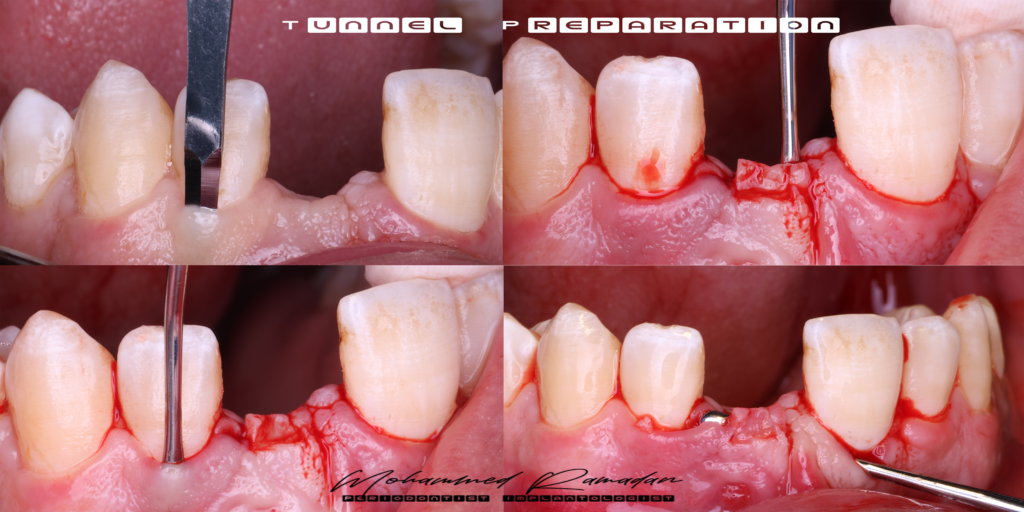

Stage Two: Soft Tissue Management and Temporization

- Implant uncovery was performed.

- Sub-epithelial connective tissue graft (CTG) placed via tunnel approach.